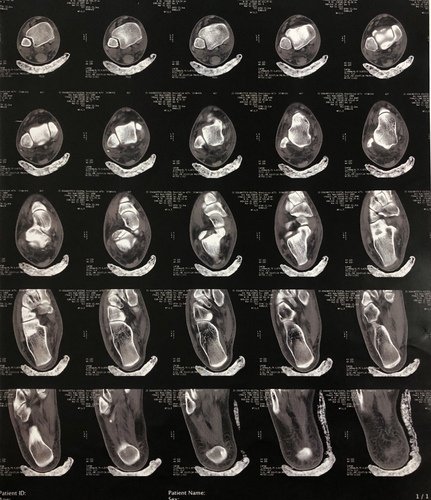

Me chamo Ythalo, tenho 25 anos, há quase um ano no dia 26/02/2022 sofri uma fratura no tornozelo do pé direito, no início pensei que não fosse nada grave, mas ao consultar me informaram que tinha um pequeno derrame articular e houve uma fratura lateral do corpo do tálus. Tive um repouso de 60 dias, e houve um pouco de alívio da dor, voltei as atividades normais, mas ao passar do tempo a dor voltou e foi aumentando cada vez mais. Fiz uma nova consulta e o médico me informou que devo fazer a cirurgia. Hoje me encontro sem trabalhar a 02 meses por não conseguir por causa da dor, e na fila do sus para a cirurgia a 05 meses, mas pelo fato de ainda não terem me chamado para a cirurgia decidi criar a Vakinha para fazer ela o mais rápido no particular, a cirurgia custa 6.000,00 e vou ter que fazer uma nova tomografia e uma nova consulta que vão ficar no valor de 1.000,00. Preciso voltar a trabalhar e voltar as minhas atividades normais, mas isso só será possível após essa cirurgia. Conto com sua ajuda e serei muito grato.